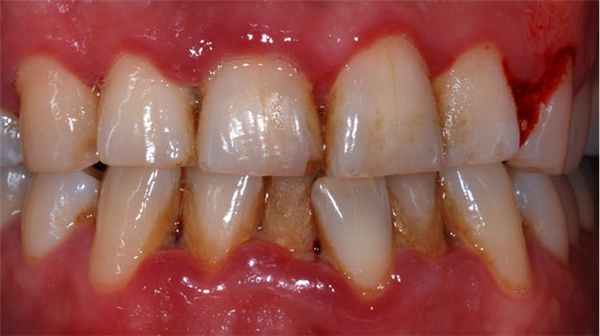

Пародонтит

Без лечения гингивит может спровоцировать развитие более тяжелого заболевания, пародонтита. Он приводит к повреждению мягких и твердых тканей, поддерживающих зубы. Как отмечают специалисты, к типичным симптомам пародонтита относятся:

- отечные, ярко-красные десны

- болезненная чувствительность десен к прикосновениям

- рецессия (опущение) десны, обнажение шеек зубов

- образование пародонтальных карманов

- выделение гноя между зубами и деснами

- неприятный запах изо рта или привкус во рту

- подвижность зубов